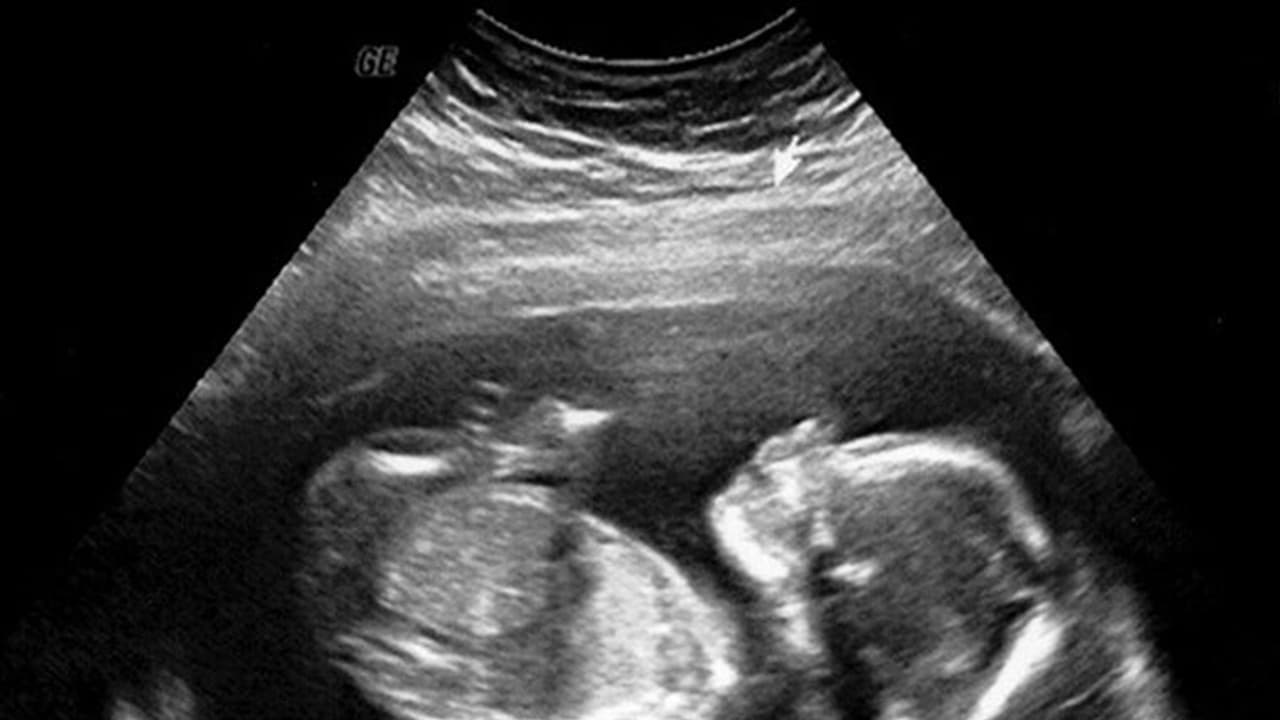

ತೀವ್ರ ಹೊಟ್ಟೆ ನೋವಿನಿಂದ ಬಳಲುತ್ತಿದ್ದ ವಾರಣಾಸಿ ಗಡ್'ವಾ ಜಿಲ್ಲೆಯ 6 ವರ್ಷದ ಬಾಲಕನನ್ನು ಇಲ್ಲಿನ ಖಾಸಗಿ ಆಸ್ಪತ್ರೆಯೊಂದಕ್ಕೆ ಚಿಕಿತ್ಸೆಗಾಗಿ ದಾಖಲಿಸಲಾಗಿತ್ತು. ತಪಾಸಣೆ ನಡೆಸಿದ ವೈದ್ಯರು ಹೊಟ್ಟೆಯಲ್ಲಿ ಗಂಟಿನಂತ ಬೆಳವಣಿಗೆಯಾಗಿದೆ ಎಂದು ಆತನ ಮನೆಯವರಿಗೆ ಆಪರೇಷನ್ ಮಾಡಬೇಕೆಂದಿದ್ದರು. ಆದರೆ ಆಪರೇಷನ್ ವೇಳೆ ವೈದ್ಯರೇ ಬೆಚ್ಚಿ ಬಿದ್ದಿದ್ದು, ಬಾಲಕನ ಹೊಟ್ಟೆಯಲ್ಲಿ ಸತ್ತ ಭ್ರೂಣ ಪತ್ತೆಯಾಗಿದೆ. ಆದರೆ ಇಂತಹ ಪ್ರಕರಣ ಈ ಮೊದಲೂ ಬೆಳಕಿಗೆ ಬಂದಿವೆ ಎಂದು ತಿಳಿಸಿದ ವೈದ್ಯರು ಪ್ರತಿ 5 ಲಕ್ಷದಲ್ಲಿ ಒಂದು ಮಗುವಿಗೆ ಹೀಗಾಗುತ್ತದೆ.

ಇದೊಂದು ಅಪರೂಪದ ಸಂಗತಿ ಎಂದು ವೈದ್ಯರು ತಿಳಿಸಿದ್ದರೂ ಮಗುವಿನ ಹೊಟ್ಟೆಯಲ್ಲಿ ಭ್ರೂಣವಿರಲು ಹೇಗೆ ಸಾಧ್ಯ? ಎಂಬ ಪ್ರಶ್ನೆ ಕಾಡುತ್ತದೆ. ಈ ಪ್ರಶ್ನೆಗೆ ಉತ್ತರ ನೀಡಿರುವ ವೈದ್ಯರು ಇಂತಹ ಮಕ್ಕಳು ತಾಯಿಯ ಹೊಟ್ಟೆಯಲ್ಲಿ ಅವಳಿ ಜವಳಿ ಇರುತ್ತವೆ. ಆದರೆ ಕೆಲ ಕಾರಣಗಳಿಂದ ಒಂದು ಮಗುವಿನ ಬೆಳವಣಿಗೆ ಆಗುವುದಿಲ್ಲ. ಹೀಗಾಗಿ ಸಶಕ್ತವಾಗಿರುವ ಭ್ರೂಣ ವಿಕಾಸಗೊಳ್ಳದಿರುವ ಭ್ರೂಣದ ಮೇಲೆ ಹಿಡಿ ಸಾಧಿಸಿಕೊಳ್ಳುತ್ತದೆ ಹಾಗೂ ಅದರ ಹೊಟ್ಟೆಯಲ್ಲೇ ಬೆಳೆದುಕೊಳ್ಳುತ್ತದೆ. ರಿತೇಶ್'ನೊಂದಿಗೆ ಹೀಗೇ ಆಗಿದೆ ಎಂದಿದ್ದಾರೆ.